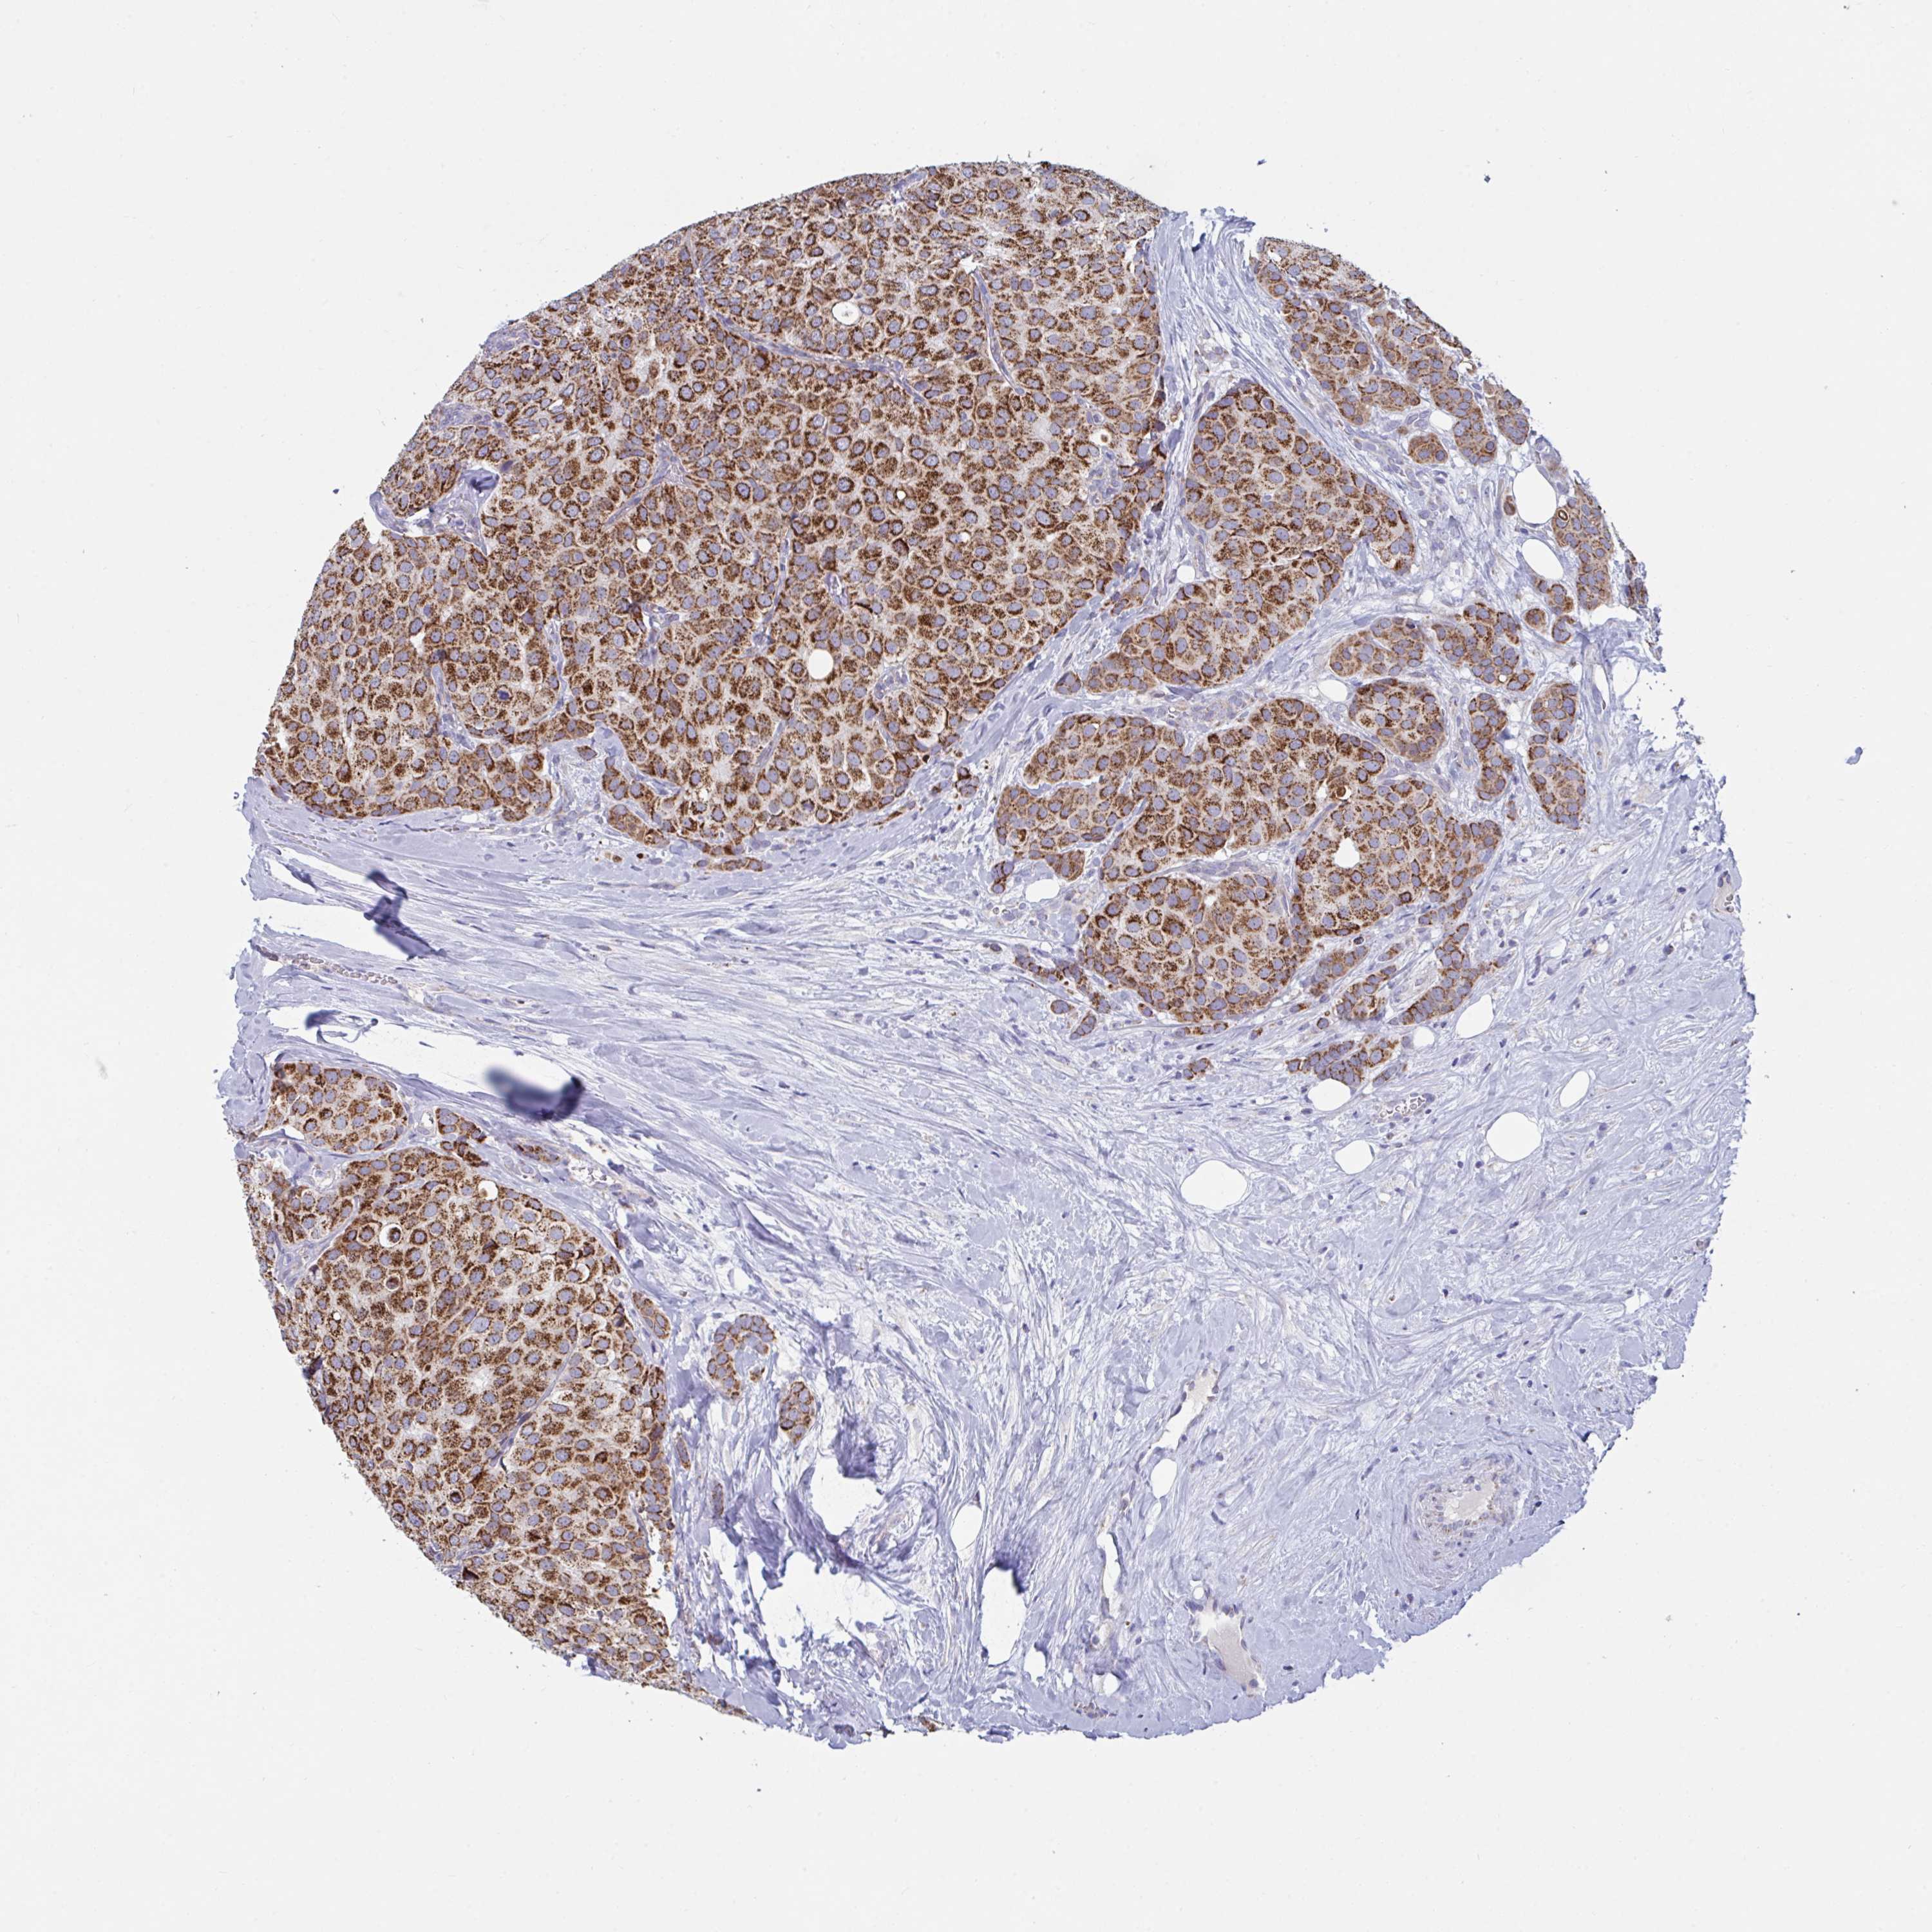

CANCER BREAST CANCER Show tissue menu

BRCA TCGA BRCA VALIDATION PROTEIN EXPRESSION

Breast cancer

Human cancer